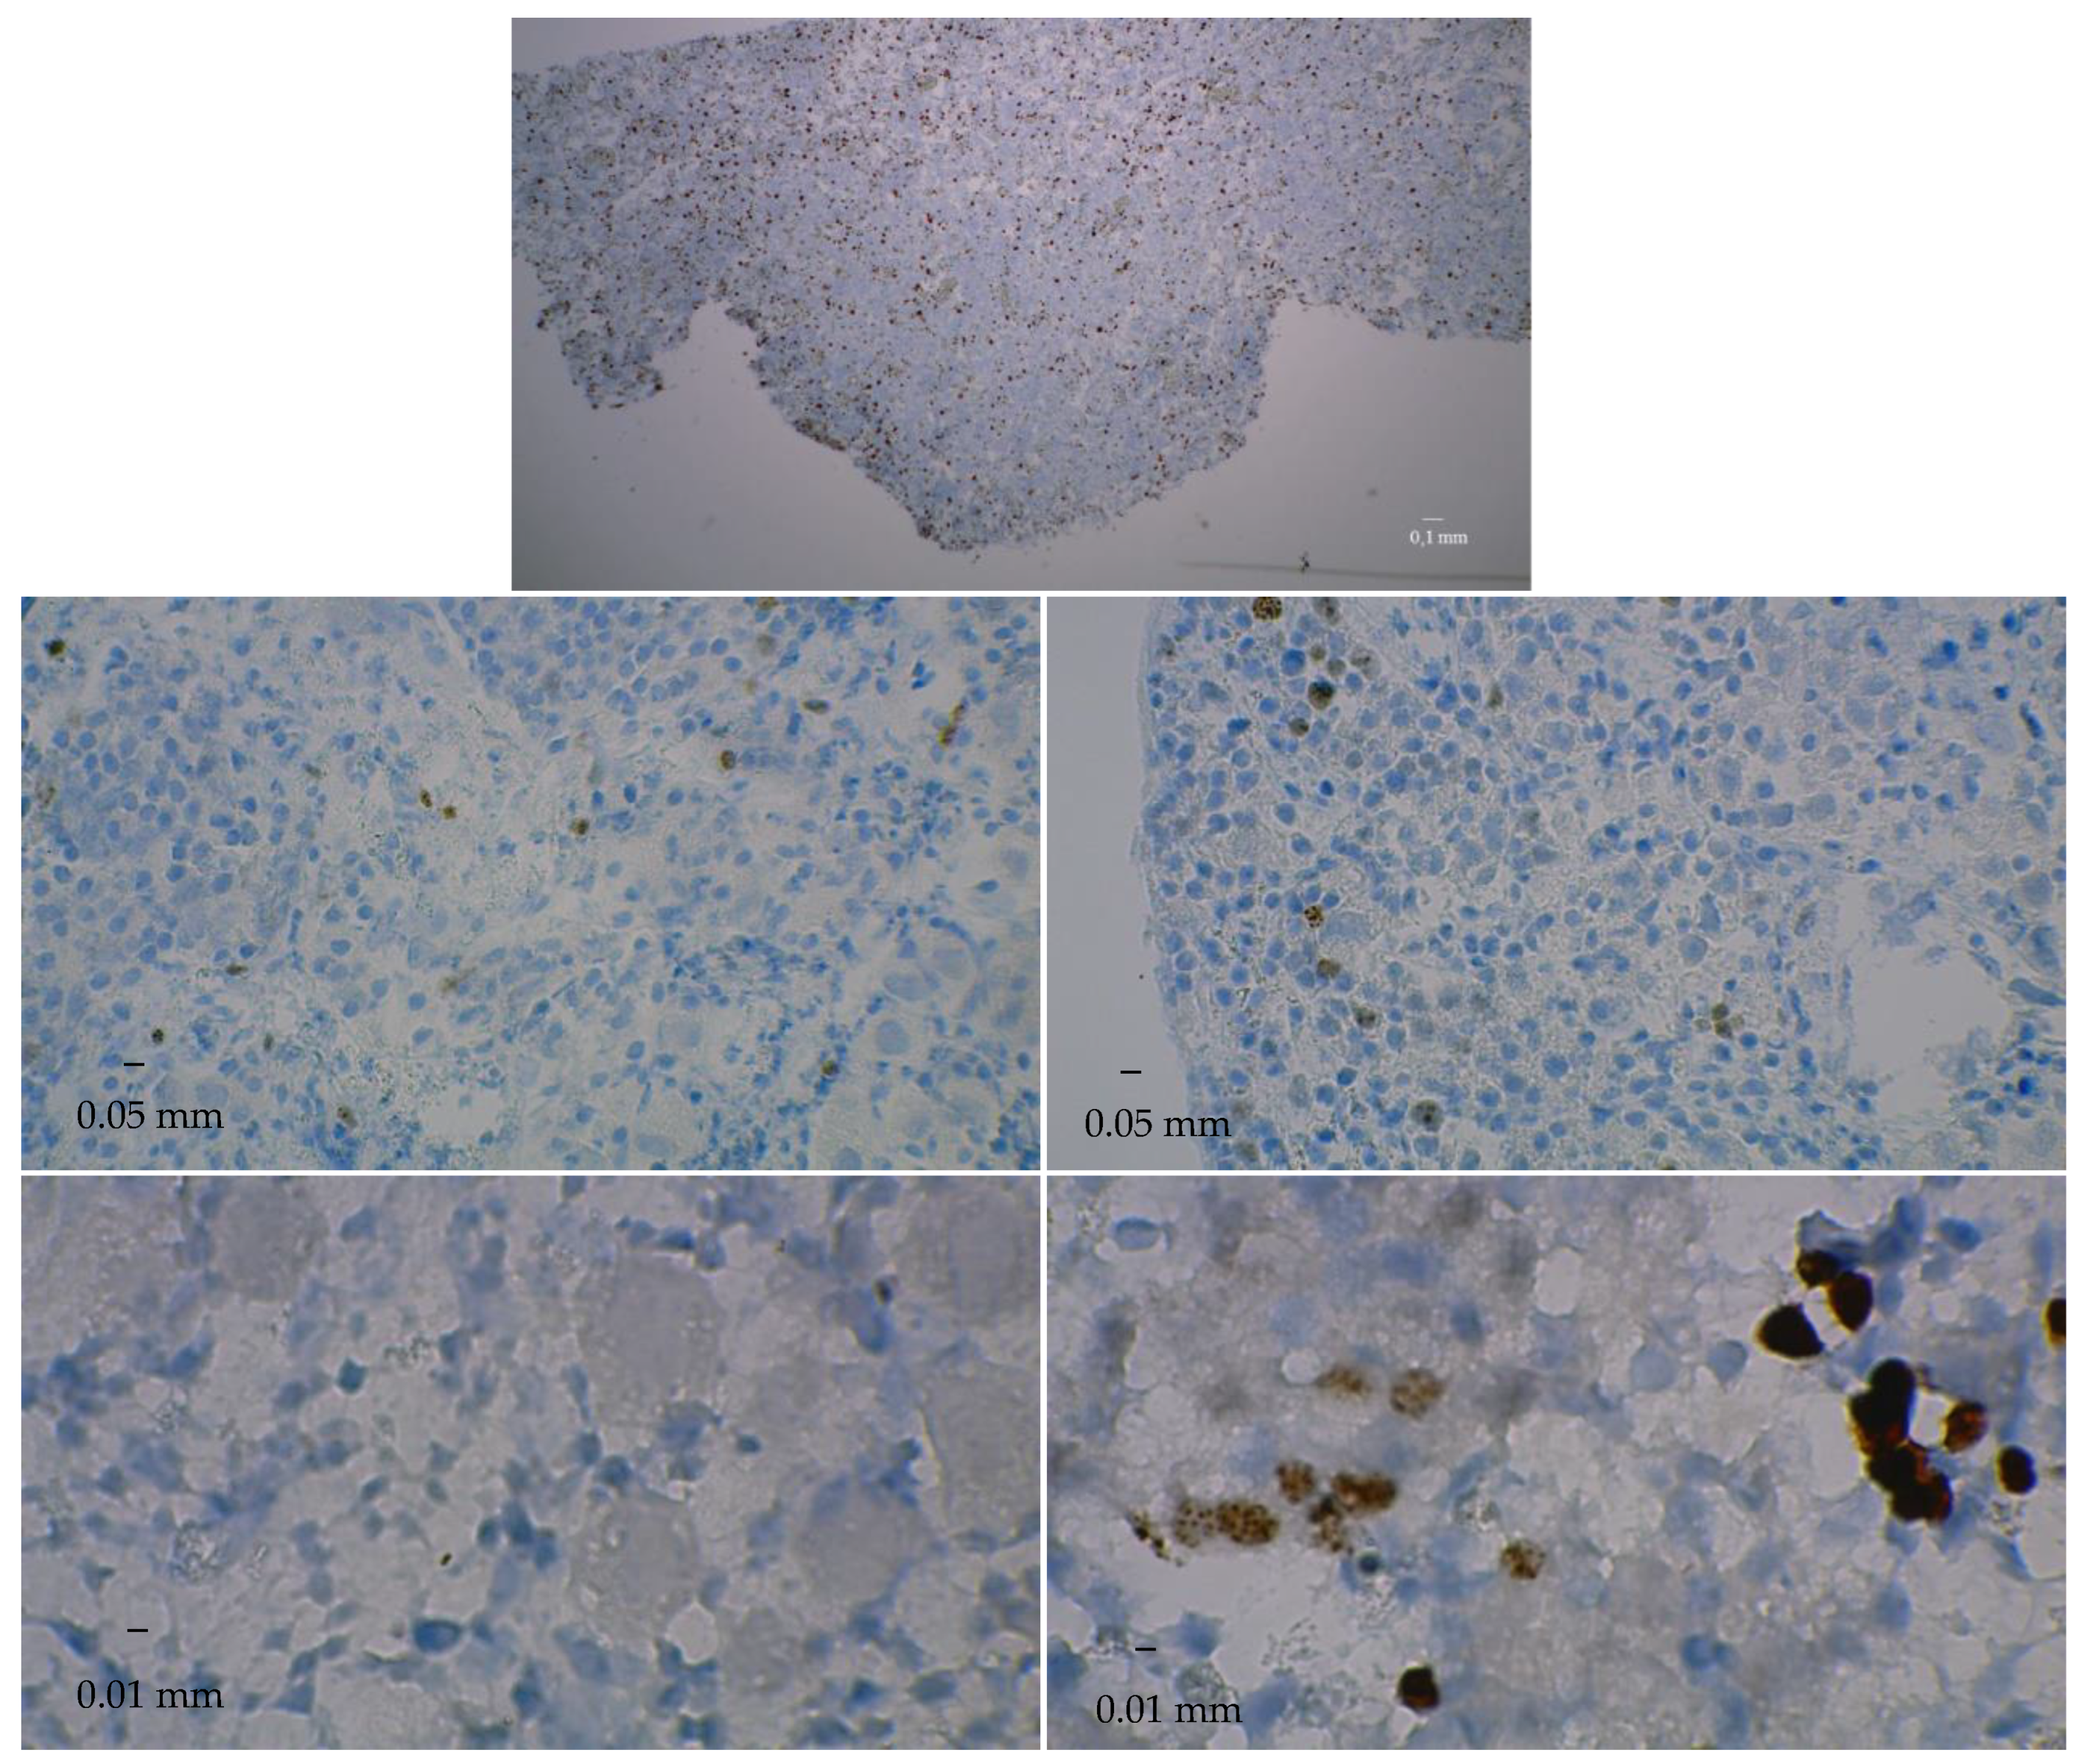

3.3. Immunostaining for Cell Apoptosis